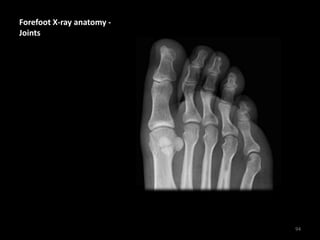

Forefoot X-ray anatomy -

Joints

94

MTPJ = Metatarsophalangeal

IPJ = Interphalangeal Joint

(of big toe only)

PIPJ = Proximal

Interphalangeal Joints

DIPJ = Distal Interphalangeal

Note the medial side

sesamoid is 'bipartite' (in 2

parts) - this is a common

normal variant - not a

fracture